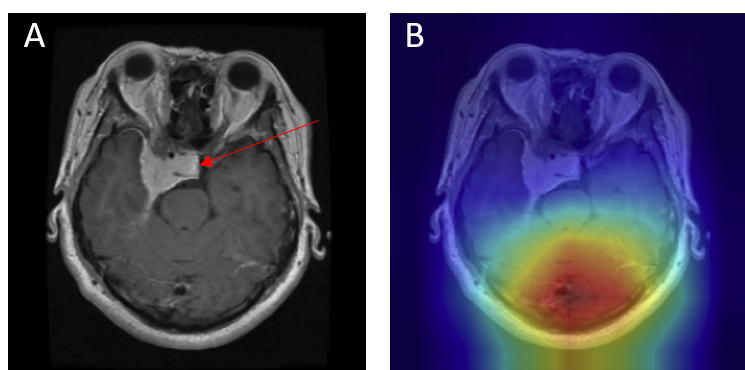

Grad-CAM visualizations of correctly classified cases confirm that the model focuses on regions consistent with radiological expectations. In these overlays, warmer colors (red and orange) highlight the areas where the network places the greatest emphasis during prediction, while cooler colors (blue) correspond to regions with minimal contribution. This distinction allows direct inspection of whether the model bases its decision on clinically relevant cues.

For gliomas, the heatmaps align with intra-axial lesions exhibiting infiltrative margins (Figure 8). Meningiomas are accurately identified at dural or peripheral attachment sites, consistent with their extra-axial presentation (Figure 9). Pituitary adenomas are localized to the sella turcica with concentrated red activation at the lesion boundaries (Figure 10). Finally, in no tumor cases, the activation maps remain diffuse or midline-focused without strong hotspots, consistent with normal anatomy (Figure 11). The correspondence between the model's attention and radiological landmarks indicates that the network is learning meaningful diagnostic features rather than relying on spurious correlations.

Figure 10: Pituitary Adenoma — original (A) vs. Grad-CAM (B), correct model prediction.

Pituitary Correct